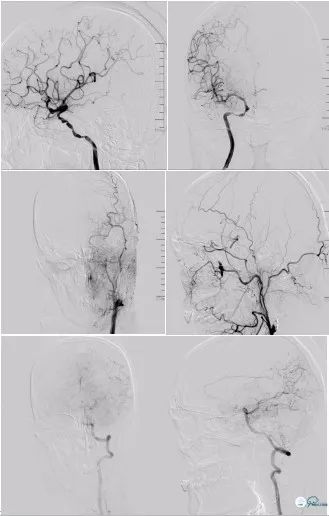

DSA(2018-06-11):右颈内动脉C4-C6段管壁不光滑,多发斑块形成,存在多发串联狭窄;右侧大脑前动脉A1纤细,显影浅淡,右侧大脑中动脉通过软脑膜支向右侧大脑前动脉代偿供血,前交通动脉开放欠佳;左颈内动脉C1段长节段闭塞,局部可见血栓影,左侧颈内动脉C6段以远经眼动脉代偿供血,可见浅淡显影,左侧大脑中动脉、左侧大脑前动脉未见显影;左锁骨下动脉造影可见左侧大脑后动脉通过软脑膜支向左侧大脑中动脉、左侧大脑前动脉代偿供血,左侧后交通未见开放(图5)